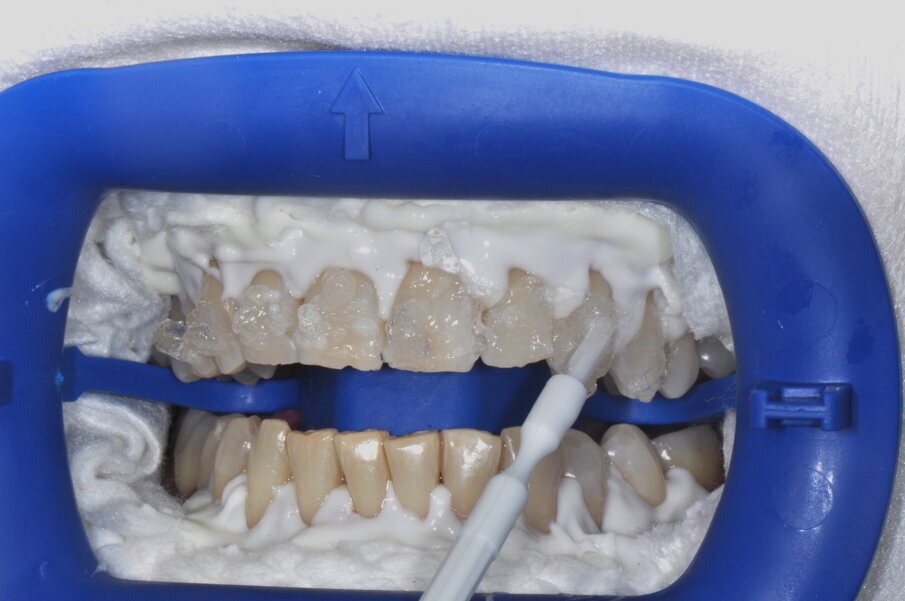

- Isolamento del campo operatorio: applicare la diga liquida su tutta la gengiva e polimerizzare;

- Applicazione del gel Zoom su tutto lo smalto;

- Attivazione della lampada Zoom;

- Al termine di ogni ciclo da 15 minuti, rimozione del gel con aspiratore e applicazione di nuovo gel Zoom.

- Applicazione del Whitening Accelerator PH Booster su tutto lo smalto;

- Applicazione del gel Zoom; senza sciacquare il Whitening Accelerator PH Booster fino a 4 cicli massimo;

- Attivazione della lampada Zoom.

- Al termine di ogni ciclo da 15 minuti, rimozione del gel con aspiratore e applicazione di nuovo Whitening Accelerator PH Booster seguito da gel Zoom.